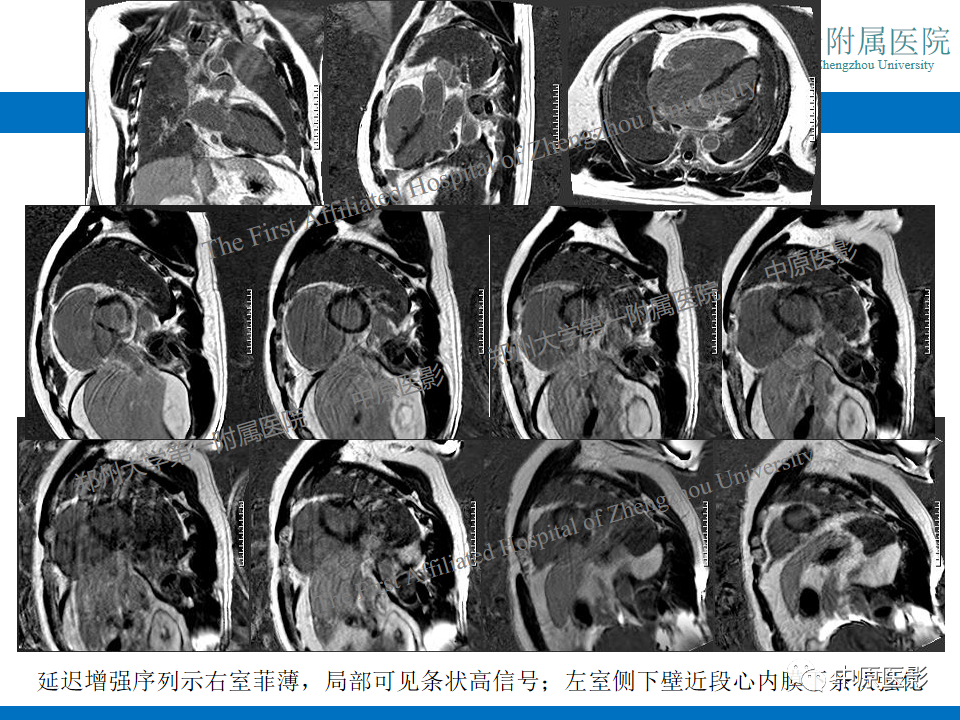

【病例】致心律失常性右室心肌病1例MR影像-3